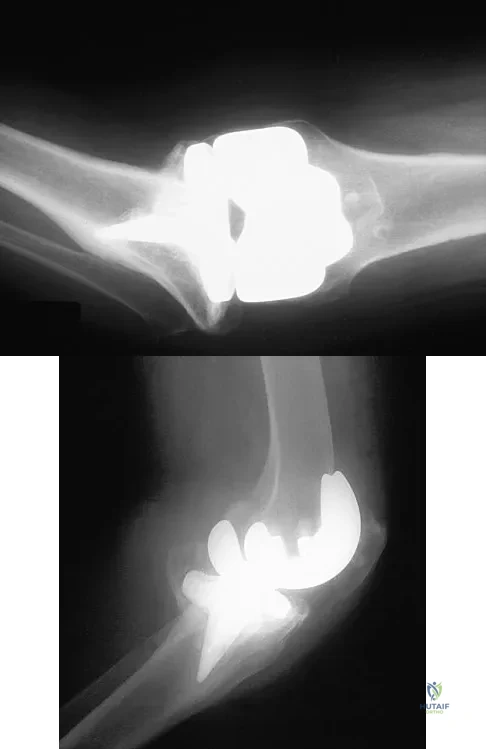

Question 85

Figures 20a and 20b show the AP and lateral radiographs of a 62-year-old man who has had hip pain for the past 3 weeks. Figure 20c shows a CT scan of the abdomen and pelvis. A needle biopsy specimen is shown in Figure 20d. Preoperative management should include which of the following?

Explanation